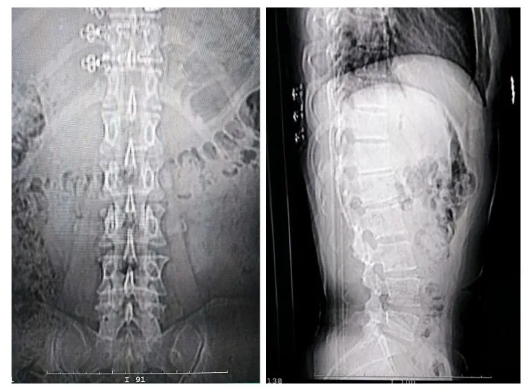

腰椎DR拍片

前几日,张女士在他人推荐下听说五洲中医院针灸推拿科治疗“腰椎间盘突出症”效果不错,于是来到了五洲中医院就诊。经过对张女士看诊,张亚东医师根据其临床特点及四诊合参,认为张女士的症状当属“痹证”,伴有“气滞血瘀证”,并结合腰部CT拍片和腰部DR拍片等相关检查后,诊断为“腰椎间盘突出症”。